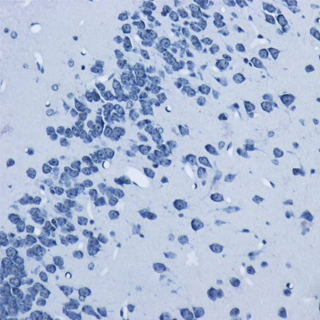

正常情況下,除脂肪細胞外其他細胞內-般不見或僅見少量脂滴。在病理狀態下如這些細胞中出現脂滴或脂滴明顯增多,特別是在心、肝.腎等實質器官發生脂肪變性時,胞漿內出現大小不一的空泡, 這時常需鑒別空泡性質,用脂肪染色來區分是脂肪變性還是水樣變性或糖原貯留。在動脈粥樣硬化時,內皮細胞下的脂質沉著,用脂肪染色能將脂質清晰地顯示出來。由脂肪組織病變所弓|起的脂肪栓塞可用脂肪染色顯示栓子內的脂質,從而確診脂肪栓塞。用于腫瘤組織的鑒別診斷,由脂肪組織所發生的腫瘤在與其他組織來源的腫瘤相區分時,可以借助脂肪染色,脂肪組織所發生的腫瘤,脂肪染色為陽性。并可根據所顯示的細胞形態特點與類似腫瘤進行鑒別,腎透明細胞癌與腎上腺瘤,卵巢纖維瘤與卵泡膜細胞瘤。皮脂腺瘤與鱗狀細胞癌的鑒別診斷有意義。

實驗結果:

脂滴呈橘紅色至鮮紅色:細胞核呈深藍色。